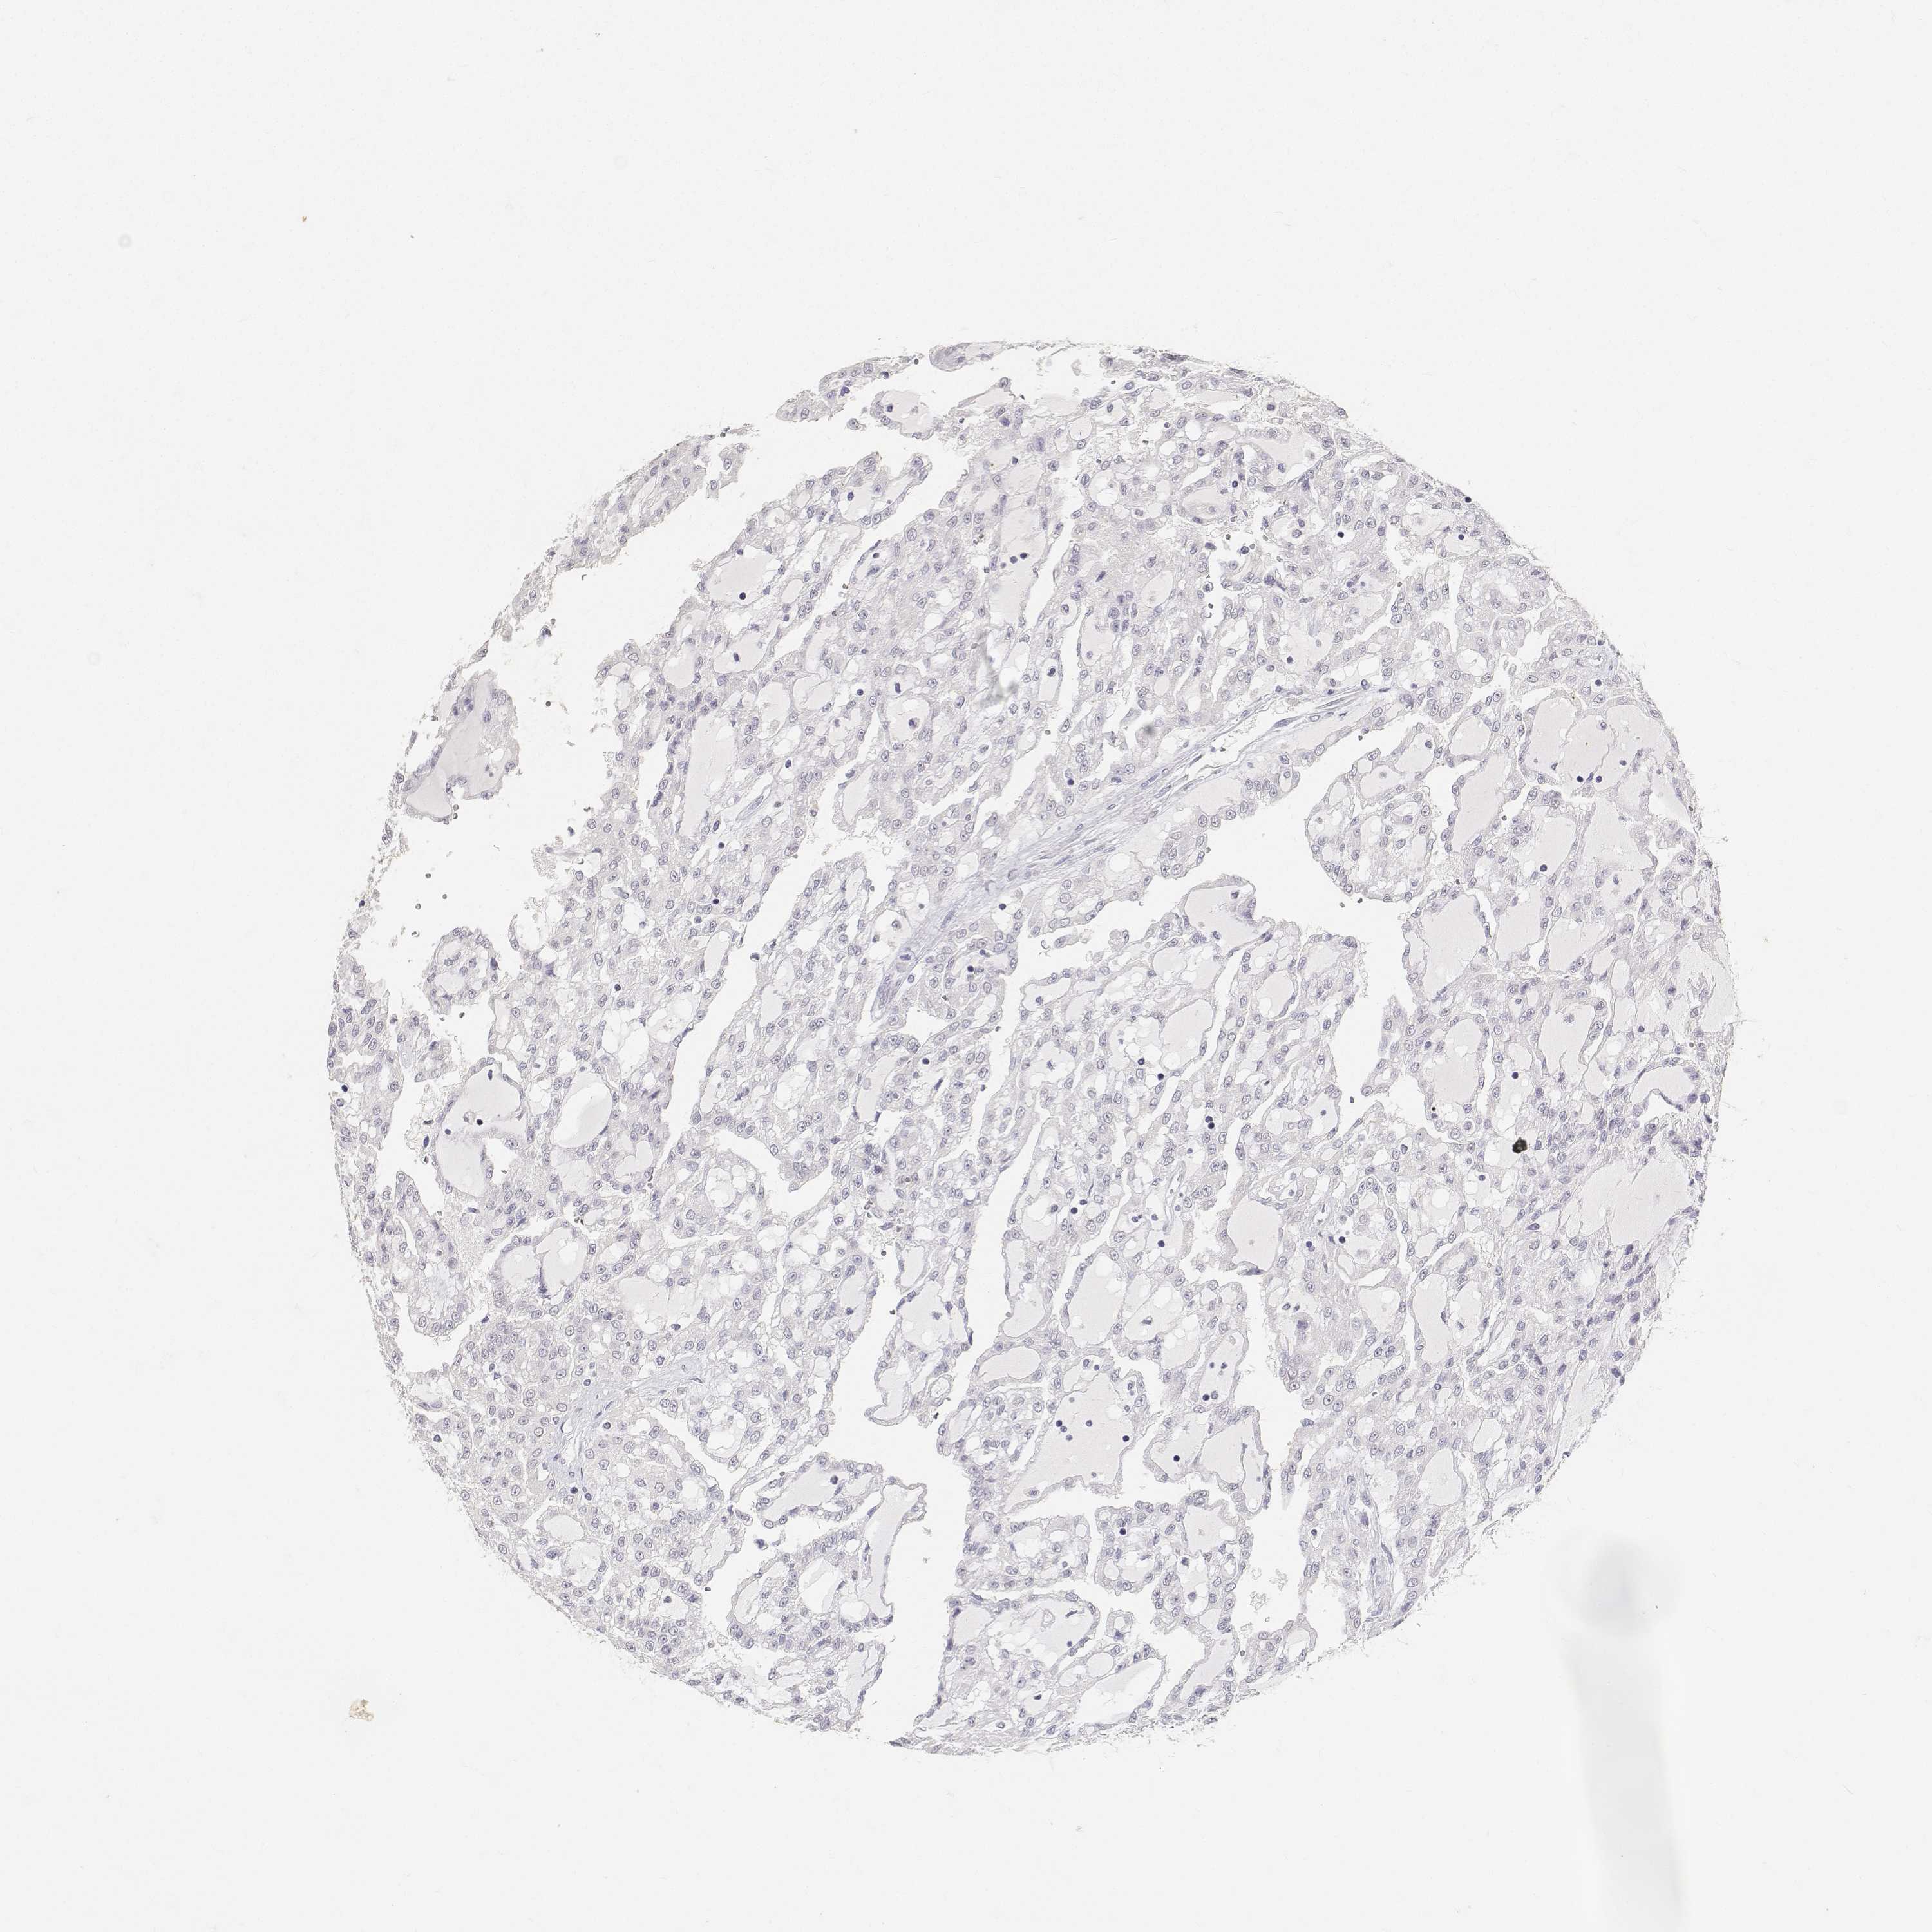

KIDNEY RENAL CLEAR CELL CARCINOMA (VALIDATION) - Interactive survival scatter ploti

The Survival Scatter plot shows the clinical status (i.e. dead or alive) for all individuals in the patient cohort, based on the same data that underlies the corresponding Kaplan-Meier plots. Patients that are alive at last time for follow-up are shown in blue and patients who have died during the study are shown in red.

The x-axis shows the expression levels (FPKM) of the investigated gene in the tumor tissue at the time of diagnosis. The y-axis shows the follow-up time after diagnosis (years). Both axes are complimented with kernel density curves demonstrating the data density over the axes. The top density plot shows the expression levels (FPKM) distribution among dead (red) and alive patients (blue). The right density plot shows the data density of the survived years of dead patients with high and low expression levels respectively, stratified using the cutoff indicated by the vertical dashed line through the Survival Scatter plot. This cutoff is automatically defined based on the FPKM cutoff that minimizes the p-score. The cutoff can be changed by dragging the vertical line or by entering a cutoff value in the square labeled "Current cut-off".

Under the Survival Scatter plot the p-score landscape (black curve; left axis) is shown together with dead median separation (red curve; right axis). Dead median separation is the difference in median mRNA expression between patients who have died with high and low expression, respectively. It is calculated as follows: median FPKM expression of dead patients with high expression - median FPKM expression of dead patients with low expression. This is intended to aid the user in visually exploring custom cutoffs and the associated p-scores and dead median separation.

Individual patient data is displayed and can be filtered by clicking on one or more of the category buttons on the top of the page. Categories describing expression level and patient information include: high, low, alive, dead, female, male and tumor stages. The scale of the x-axis can be toggled between linear and log-scale by clicking on the "x log" button. Mouse-over function shows TCGA ID, patient information and mRNA expression (FPKM) for each patient.

& Survival analysisi

Kaplan-Meier plots summarize results from analysis of correlation between mRNA expression level and patient survival. Patients were divided based on level of expression into one of the two groups "low" (under cut off) or "high" (over cut off). X-axis shows time for survival (years) and y-axis shows the probability of survival, where 1.0 corresponds to 100 percent.

PAEP is validated prognostic, high expression is unfavorable in Kidney Renal Clear Cell Carcinoma (validation)

: 0.84

Average pTPM 4.7

Number of samples 100